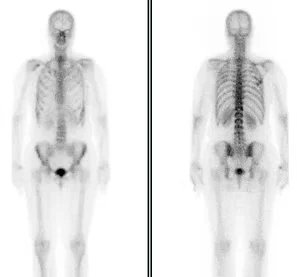

Bone Scans

Bone scans are a sensitive test for evaluating almost any process affecting the skeleton, like bone tumors, fractures, infection, inflammation and many other conditions. The study may be abnormal days or weeks before there are symptoms or changes on plain x-rays. The study is usually completed at one visit, requiring anywhere from one to several hours depending on the reason for the study. SPECT imaging can be performed to give three-dimensional imaging that can be compared directly to images from a CT or MRI. Serial examinations over months or years can document the extent or severity of a disease process over time.